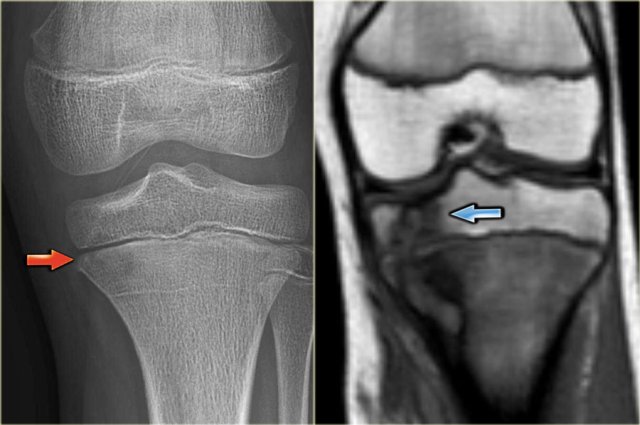

On the left images of a CMF.

There is an eccentric osteolytic lesion in the metaphysis of the proximal tibia.

On the inner side there is a sclerotic margin.

On the outer side there is a regular cortical destruction with peripheral bone layer.

The MR also shows a sclerotic margin with low signal intensity.

Discriminators :

- Mention when an NOF is mentioned.